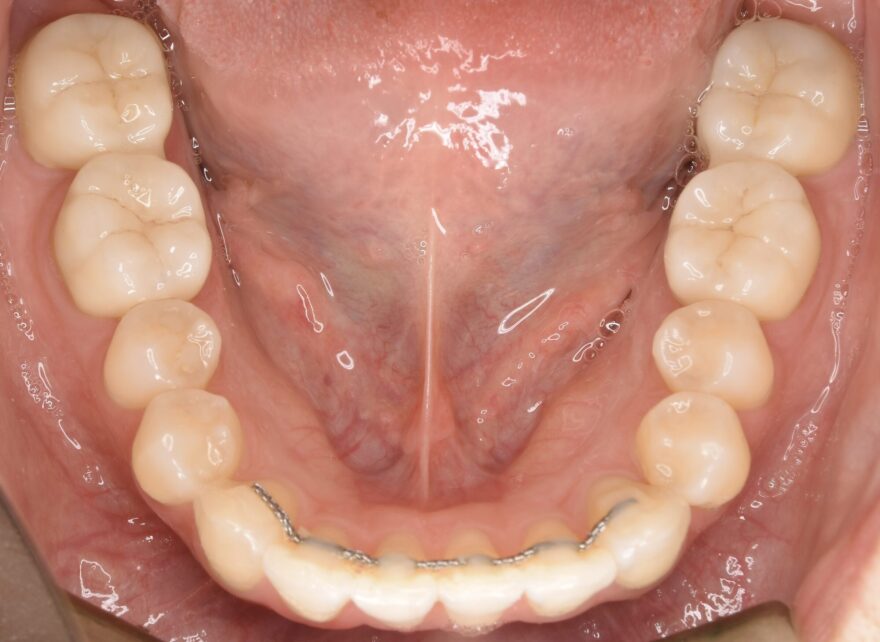

治療後の口腔内写真

矯正治療後に、大きく樹脂の入った歯を、セラミックで被せました。

マウスピース矯正とセラミック治療により、理想的な噛み合わせになりました。

左右差もなく緊密に噛み合っていることが分かります。

白くて美しいセラミック歯が4本入りました。

歯並びの安定性を優先してセラミック歯は連結しています。

こちらも、4本のセラミック歯が入りました。

上顎と同じく、歯並びの安定性を優先してセラミック歯は連結しています。